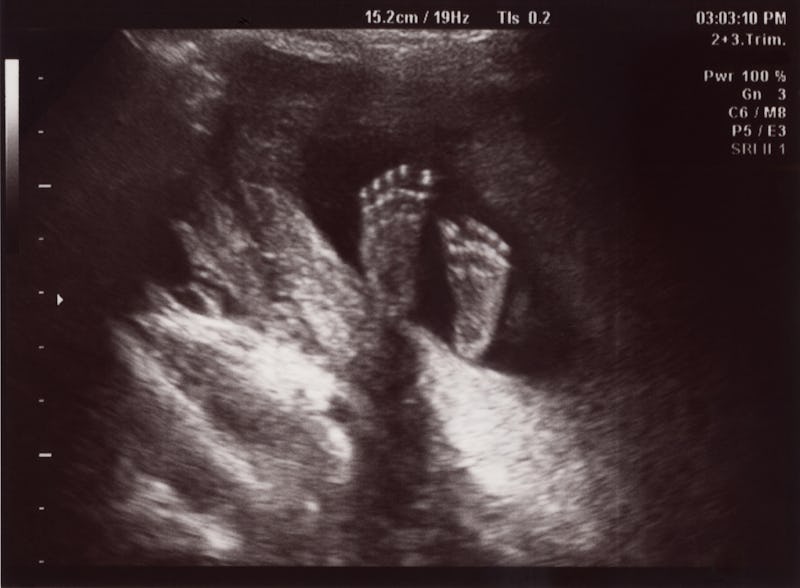

Ultrasound exams are notoriously inaccurate for predicting the weight of your baby. Sadly most women have cycles between 21-35 days and when this method is applied to calculate their due dates the dates are wrong. My first ultrasound showed empty sac a week ago. Its important to know there is a recognised 15 error in ultrasound fetal weight estimation. This means that conception did not take place on 14-16 day cycle and a week or two later and the woman just came on the ultrasound too early so the fetus was not seen. Gender Could Ultrasound Be Wrong Babycenter.

Ultrasound scans are generally more accurate for assessing your babys size during the first half of pregnancy. She didnt use the vaginal probe. My first ultrasound showed empty sac a week ago. Its important to know there is a recognised 15 error in ultrasound fetal weight estimation. While gender prediction is much more accurate during the 20-week ultrasound theres still a chance it can be wrong. Prenatal Ultrasound Scans.

One of the most important reasons for prenatal visits and for doing an ultrasound examination is to estimate the fetal size of your baby. Miscarriages are predicted by doctors when a womans embryo or gestational sac seems too small and when an ultrasound shows no fetal heartbeat. This can happen for example if the baby is developing slowly and the tubercle hasnt begun to point up or the umbilical cord is mistaken for a penis. Ultrasound exams are notoriously inaccurate for predicting the weight of your baby. But the ultrasound tech said I was measuring 65 weeks. Umbilical Cord Mistaken For Boy Parts April 2015 Babies Forums What To Expect Page 2.